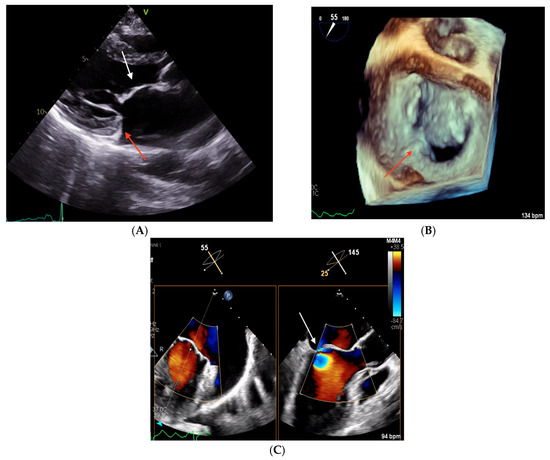

2.2. Clinical Case 2

2.3. Clinical Case 3